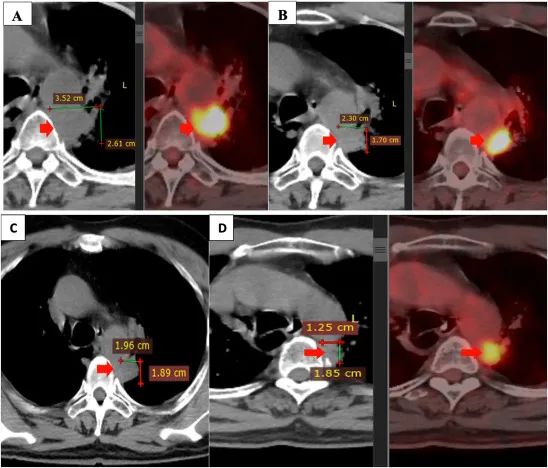

注:聯(lián)合治療前后的原發(fā)性腫瘤。原發(fā)腫瘤在二線治療(4 個周期的 alimta,卡鉑,可瑞達)后進展(A)。原發(fā)腫瘤在治療結(jié)束時與自體 NK 細胞療法,吉西他濱,貝伐珠單抗(B),3 個月后(C),6 個月(D)組合減少。

患者在 4 至 5 個月內(nèi)、每 3 周內(nèi)和在此期間每 3 周接受 6 個療程的自體 NK 細胞輸注。在此期間,患者在第 1 天和第 8 天(每 3 周 2 個周期)接受阿瓦斯?。?/span>400mg,每 3 周 2 個周期)聯(lián)合吉西他濱(1800mg)治療,干咳和胸痛癥狀消失?;颊唢嬍沉己?,生活質(zhì)量顯著提高。聯(lián)合治療期間未觀察到明顯副作用,肝腎功能評估在正常范圍內(nèi)。

2021 年 3 月和 2021 年 9 月進行的 PET/CT 掃描顯示,與聯(lián)合治療前相比,原發(fā)腫瘤的大小顯著縮小。此外,兩側(cè)均未發(fā)現(xiàn)縱隔或鎖骨上淋巴結(jié)。